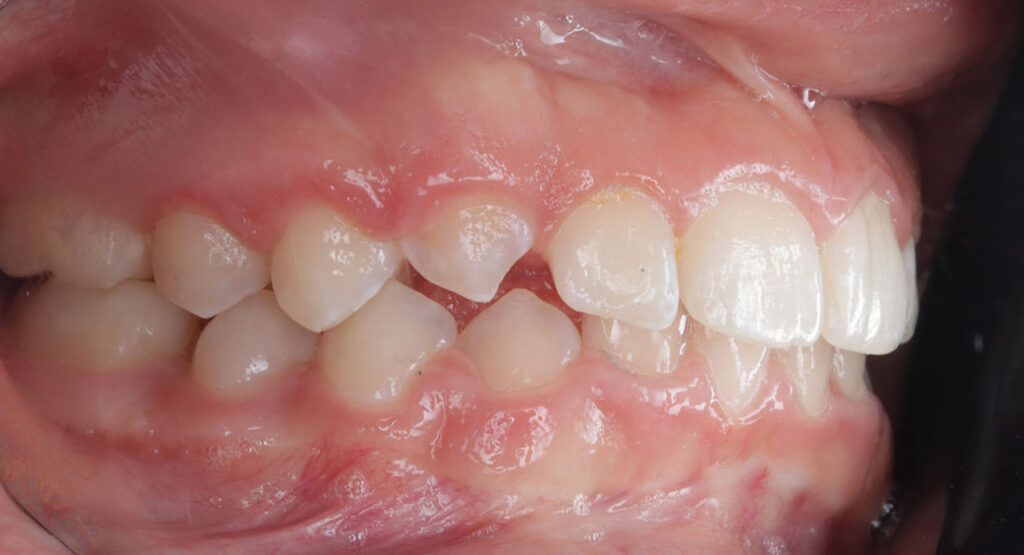

Case report of a 9-year-old female patient in the intermediate phase of mixed dentition. The patient presents with moderate upper and lower crowding, narrow arches, Class II molar relationship on the right side, premature loss of tooth 83, deviation of the lower midline to the right, deep bite, and a crossbite on the right side affecting only the deciduous dentition.

The goal of the treatment was to achieve transverse development of both arches, proclination of upper and lower incisors to correct the deep bite, and to create space for the blocked tooth.